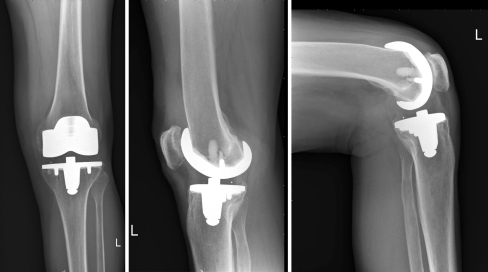

Fig. 2.

Radiographs of the Innex prosthesis five years after replacement in a 64-year-old woman. Left: anteroposterior view (standing); centre: lateral view (standing); right: lateral view (seated)